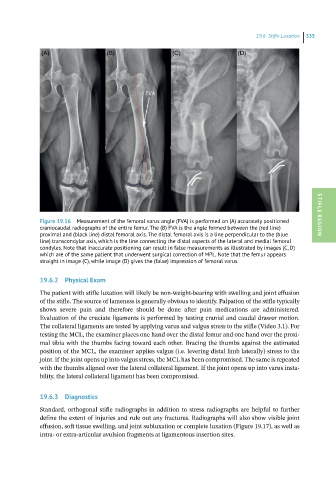

Figure 19.16 Measurement of the femoral varus angle (FVA) is performed on (A) accurately positioned STIFLE REGION

craniocaudal radiographs of the entire femur. The (B) FVA is the angle formed between the (red line)

proximal and (black line) distal femoral axis. The distal femoral axis is a line perpendicular to the (blue

line) transcondylar axis, which is the line connecting the distal aspects of the lateral and medial femoral

condyles. Note that inaccurate positioning can result in false measurements as illustrated by images (C, D)

which are of the same patient that underwent surgical correction of MPL. Note that the femur appears

straight in image (C), while image (D) gives the (false) impression of femoral varus.